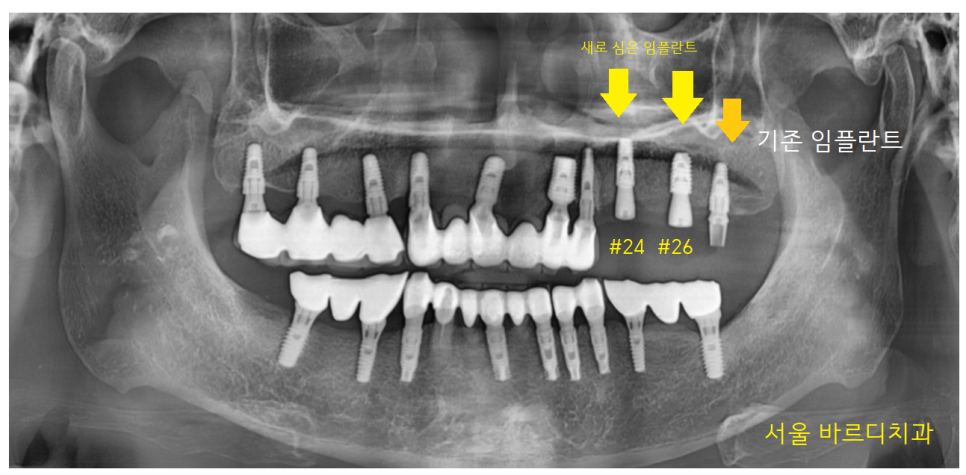

23.08.25

#24,26 임플란트 2개가 들어갔습니다.

예전에는 2개 임플란트에 4개의 어금니를 만들었지만

2개가 4개의 힘을 나눠 했다면

23.11.20

다시 하시는 만큼

3개가 4개의 일을 하도록 하였습니다.

덕풍동 치과에서 튼튼하게 보강하였습니다.